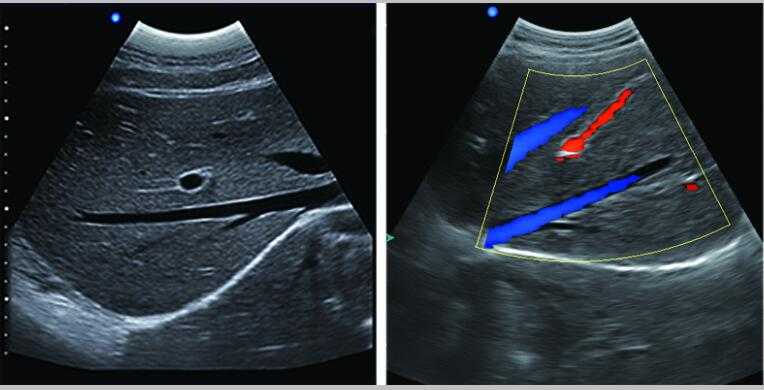

s6獸用B超機

L3-VET筆記本式獸用B超機

L3-VET便攜筆記本式獸用B超機適用探頭

S6便攜筆記本式獸用B超機適用探頭